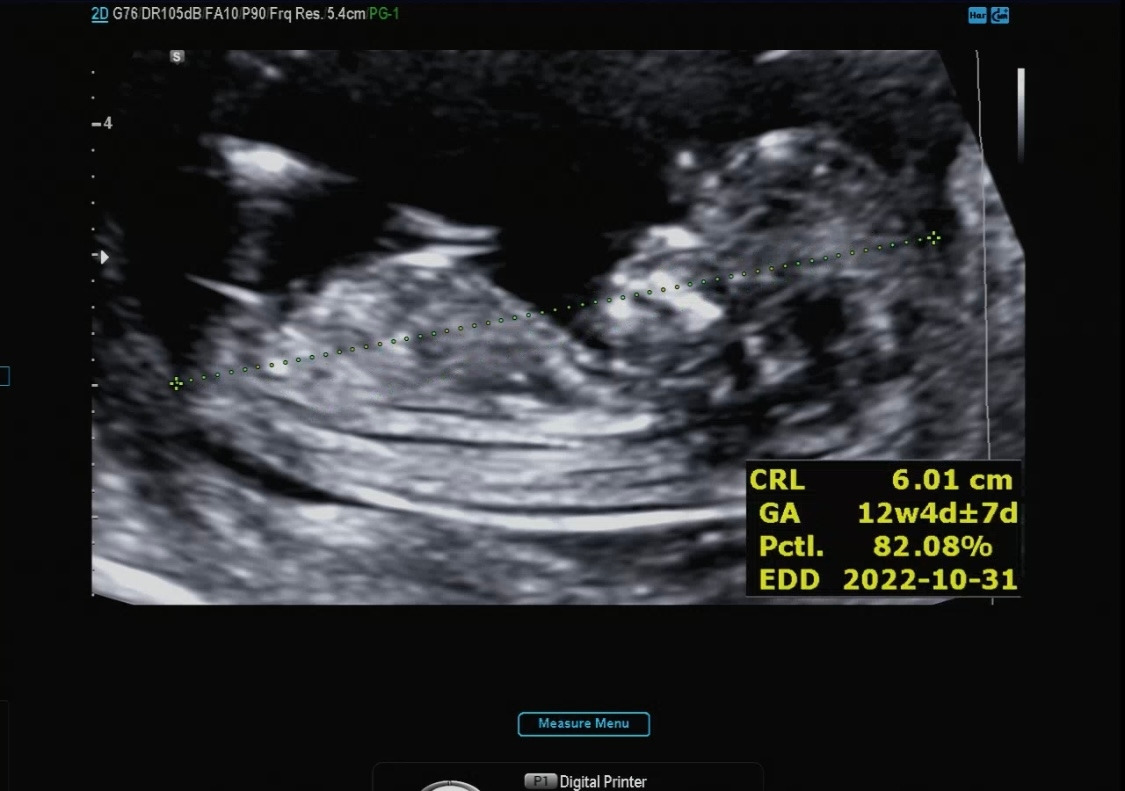

아가 사이즈 측정

머리에서 엉덩이까지의 길이

12주 차 3일 12주 차 4일이 나왔고, 원래 7일 정도의 차이는 존재한다고 알려주셨다.

사이즈는 6cm 정도로 컸더라 :)

딱 12주 차는 5.4의 자두 정도의 크기라고 베이비빌리를 통해 알고 있었다. 아마 12주 차 2일에 방문해서 아가가 조금 더 큰 거 같다. 하루하루 다르게 쑥 쑥 크고 있는 다올이의 모습이 참 신기하다.